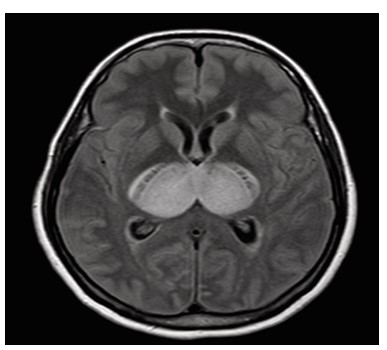

Dengue fever, a mosquito borne viral illness, is endemic in many parts of the world, particularly in tropical and subtropical regions. It is caused by four distinct serotypes (DENV 1–4) of single stranded RNA viruses from the Flaviviridae family. Although it is generally considered non-neurotropic, certain strains, especially DENV-2 and DENV-3, have been associated with neurological involvement. Neurological complications can include encephalopathy, encephalitis, meningitis, acute disseminated encephalomyelitis (ADEM), stroke, and Guillain-Barré syndrome. Dengue encephalitis, a relatively uncommon but serious manifestation, arises from direct viral invasion of neural tissue. This case report presents a patient with altered mental status and characteristic MRI findings symmetrical involvement of the thalami and cerebellum, known as the “double doughnut sign” indicative of dengue encephalitis. Cerebrospinal fluid analysis confirmed the diagnosis. Early recognition, neuroimaging, and supportive management with immunomodulation played a crucial role in the patient’s recovery. Clinicians should maintain a high index of suspicion for dengue encephalitis in endemic areas when encountering unexplained encephalopathy.